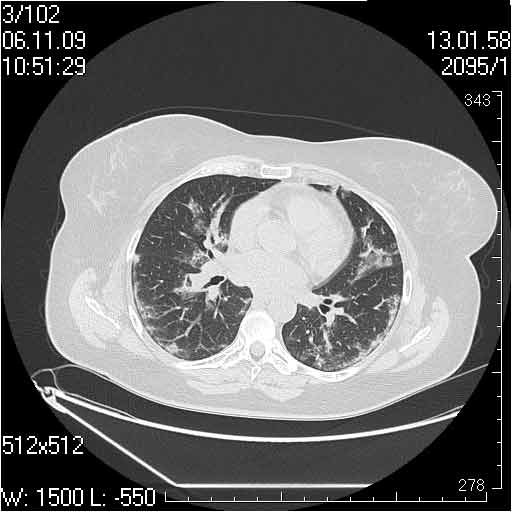

Случай №2

Мужчина 54 лет

Случай 2: картина патологических изменения довольно типична: GGOs & thickened interlobular septas = "crazy paving" sign. Наличие плотностей по типу матового стекла в сочетании с утолщением междолевых перегородок, даёт признак булыжной мостовой; на первом месте будет стоят диагноз альвеолярных протеиноз.